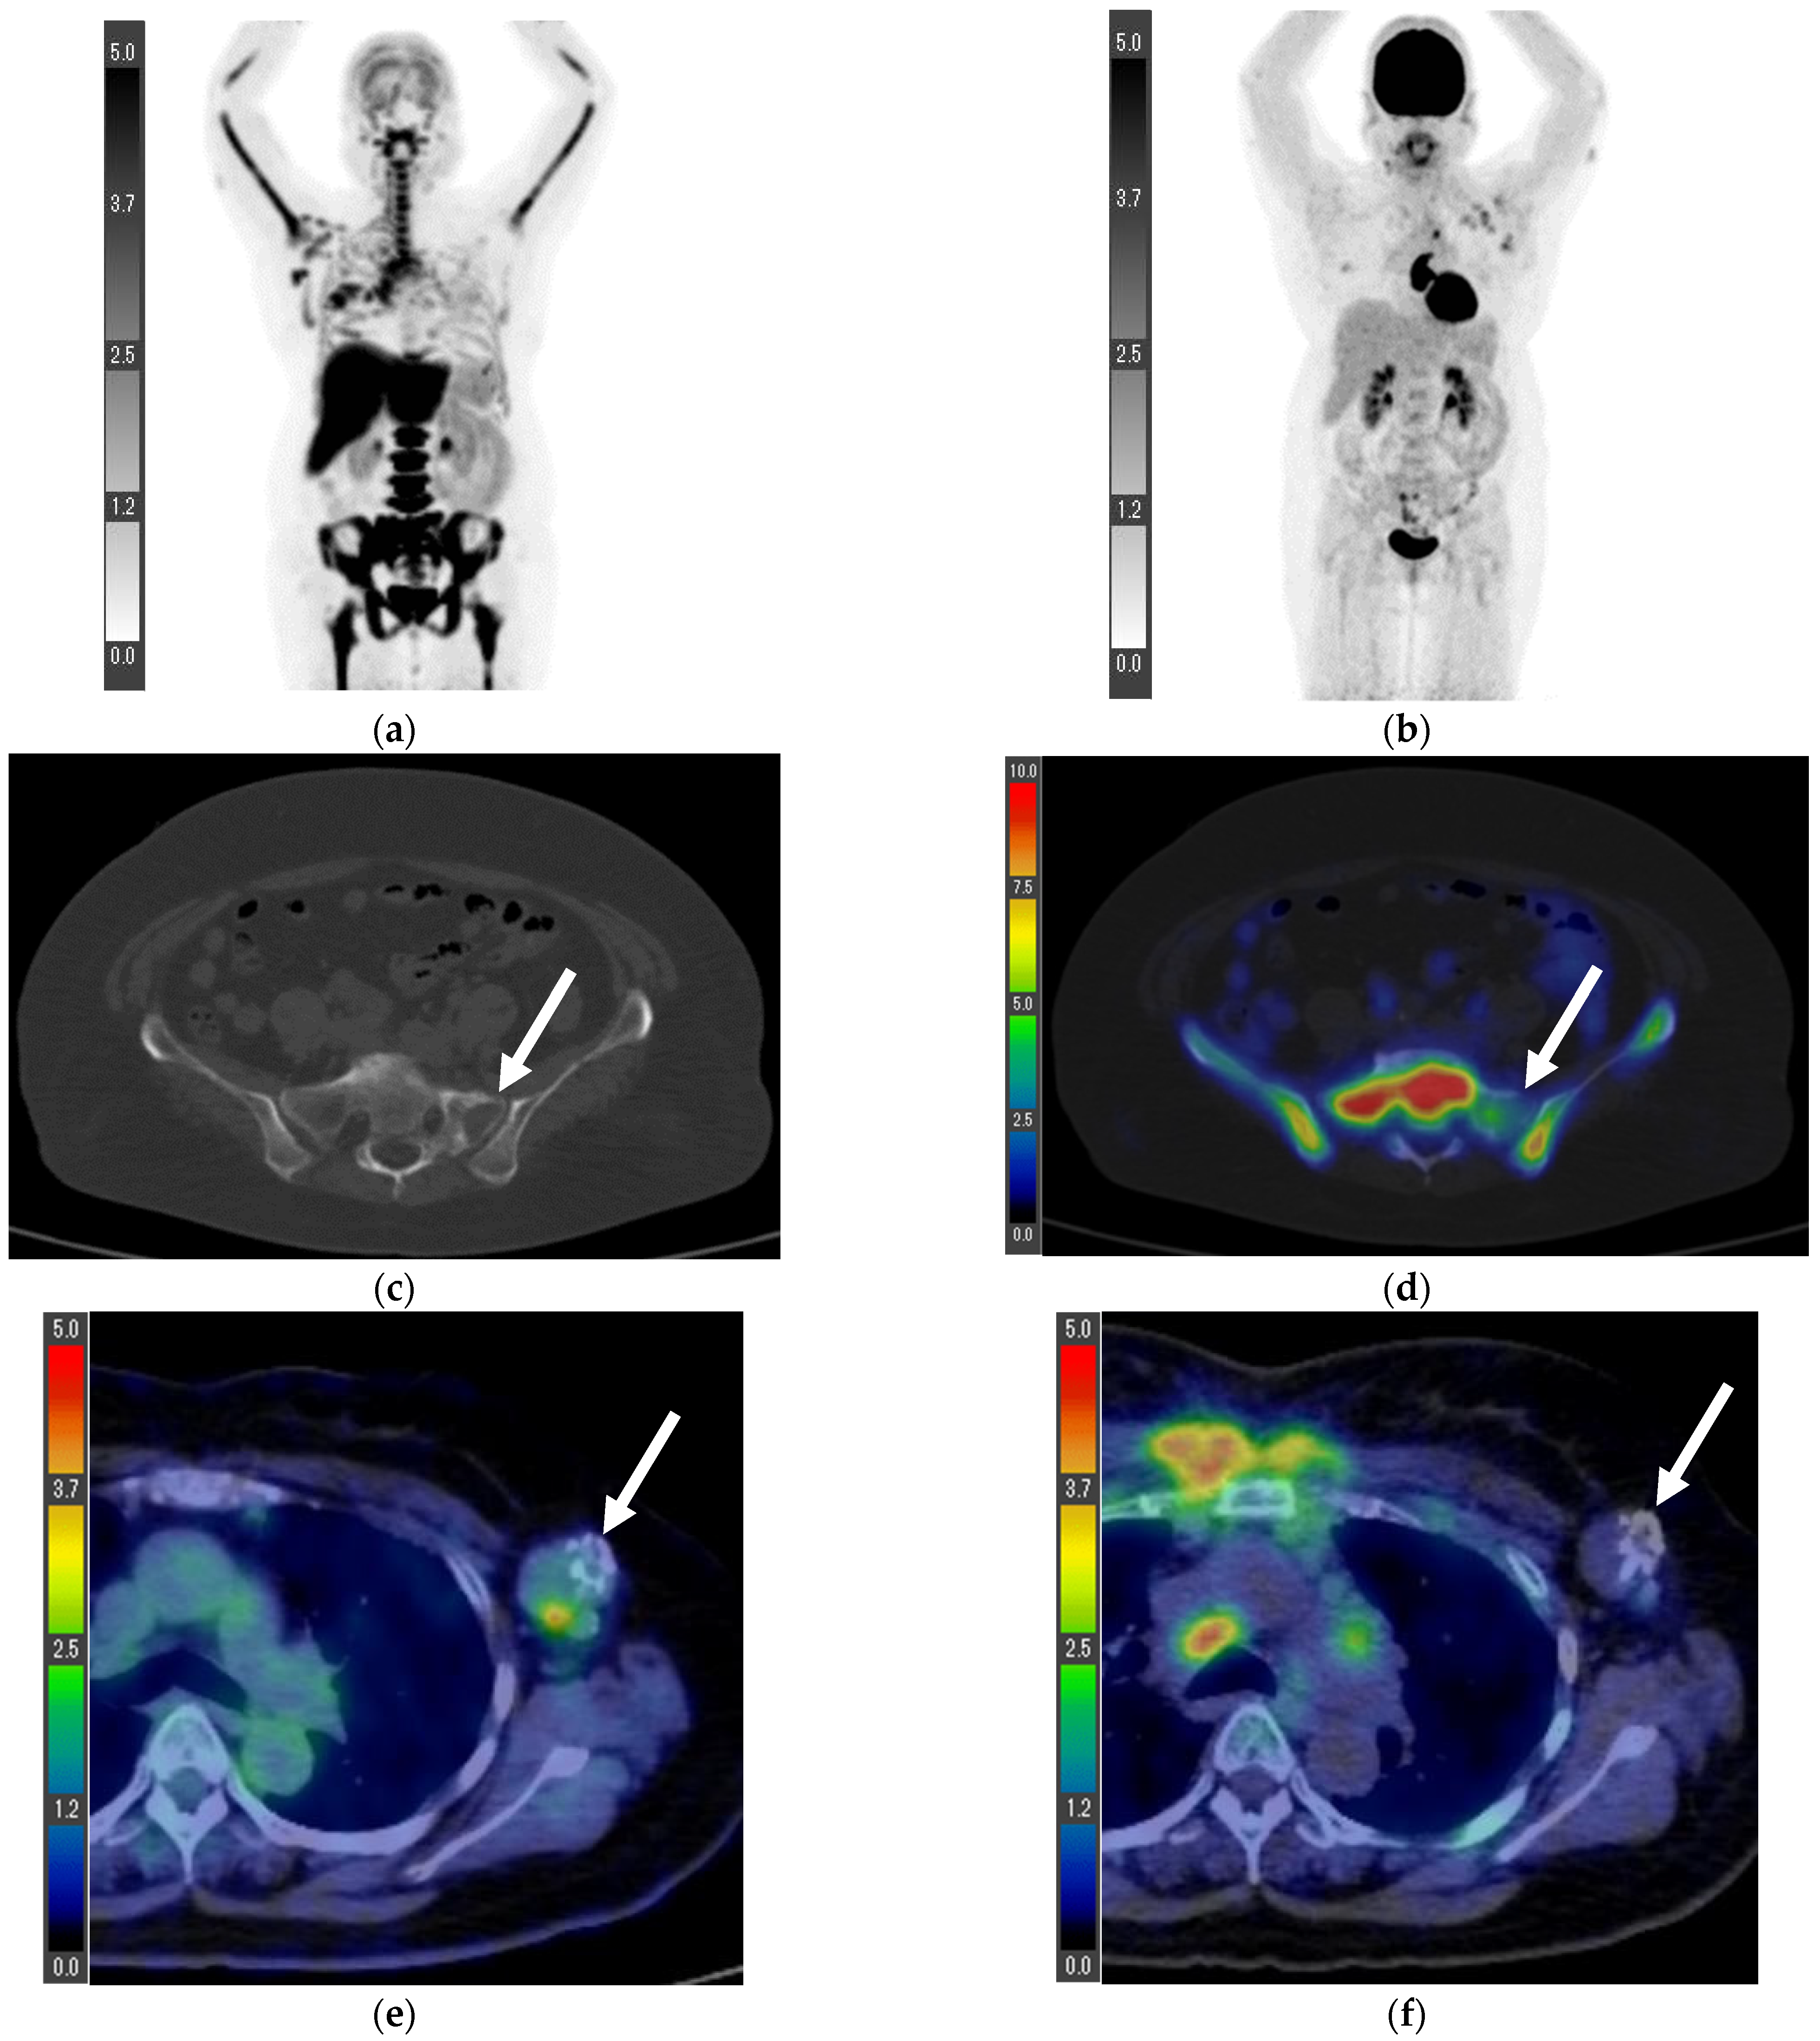

| Patient | Primary FLT | Primary FDG | LN FLT | LN FDG | Stage | Histological Diagnosis | Nuclear Grade | ER | PR | HER2 | Ki-67 (%) |

|---|---|---|---|---|---|---|---|---|---|---|---|

| 1 | 1.0 | 1.8 | 1.6 * | 3.4 * | T1cN2aM0 ** | Invasive ductal carcinoma | 1 | + | + | − | 1.0 |

| 2 | 0.6 | 1.6 | 0.7 | 0.8 | T1bN0M0 ** | Invasive ductal carcinoma | 1 | + | + | − | 6.7 |

| 3 | 2.2 | 3.1 | 0.5 | 0.6 | T1cN0M0 ** | Invasive ductal carcinoma | 2 | + | + | − | 24.6 |

| 4 | 0.4 | 1.5 | 16.7 * | 14.2 * | T1bN3aM1 *** (Lymph node and bone metastases) | Invasive ductal carcinoma | Data loss | + | + | − | Data loss |

| 5 | 3.8 | 8.3 | 1.8 | 6.3 | T2N3bM0 *** | Invasive ductal carcinoma | 1 | + | + | − | 25 |

| 6 | 4.8 | 8.4 | 1.4 | 3.2 | T4bN1M1 *** (Lumbar vertebra metastasis) | Invasive ductal carcinoma | 1 | + | + | − | 8.9 |

| 7 **** | 7.0 | 10.1 | 1.2 | 0.7 | T4bN0M0 | Invasive ductal carcinoma | Data loss | − | − | + | 59 |

| 8 ***** | - | - | 1.1 | 4.1 | N3bM1 (Lymph node, lung, and bone metastases) | Invasive ductal carcinoma | 3 | + | − | + | 29.3 |